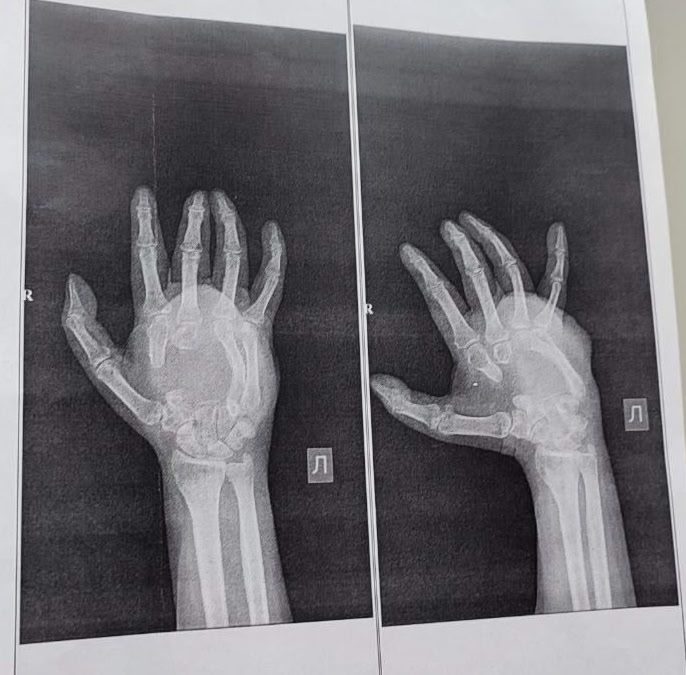

Огнестрельное ранение привело к тому, что у мужчины практически полностью утрачена основа кисти.

Он сообщил, что в результате ранения у мужчины повреждены пястные кости кисти, сухожилия и нервы.

– Врачи ККЦОЗШ им. св. Варвары уже провели первый этап восстановления — костную пластику. Для замещения серьезных дефектов (3 и 5 см!) медики использовали собственные ткани пациента из тазовой кости, – отметил Тарасов.